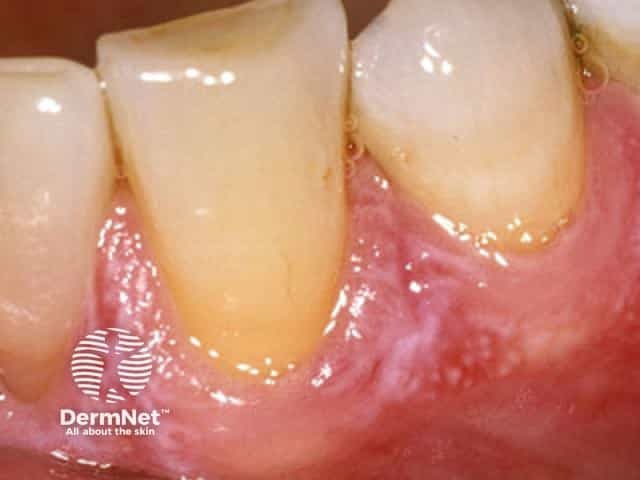

Other forms of oral lichen planus may also occur, including white lacy streaks and inflammation and peeling of the gums (desquamative gingivitis).

Erosive oral lichen planus